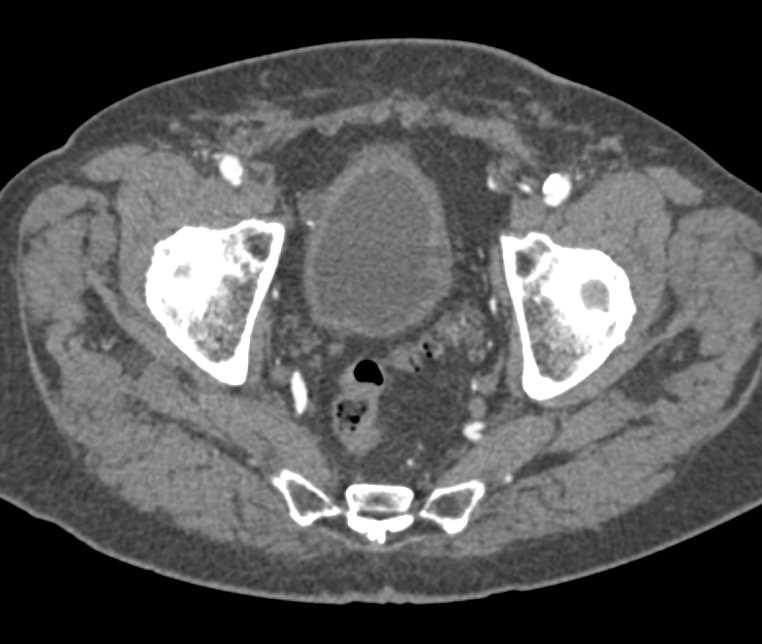

Incidental Bladder Cancer on Right Wall of the Bladder